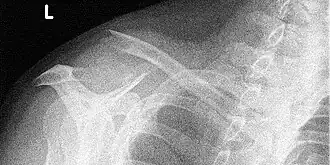

Ein Rucksackverband (auch Tornisterverband oder Claviculabandage genannt) wird zur Stabilisierung und Ruhigstellung der Schulterhaltung bei einer Klavikulafraktur (Schlüsselbeinbruch) eingesetzt. Dabei wird eine Schulterbandage zur Fixierung des Schlüsselbeins verwendet. Dieser Verband zieht die Schultern nach hinten, erzwingt eine gerade Rückenhaltung und soll damit dafür sorgen, dass das Schlüsselbein nicht zu kurz zusammenwächst und der Patient weniger Schmerzen hat. Der Verband muss täglich kontrolliert und eventuell nachgezogen oder gespannt werden.[1] (siehe Röntgenaufnahme einer lateralen Claviculafraktur). Auch eignet er sich nicht für alle Schlüsselbeinbrüche.